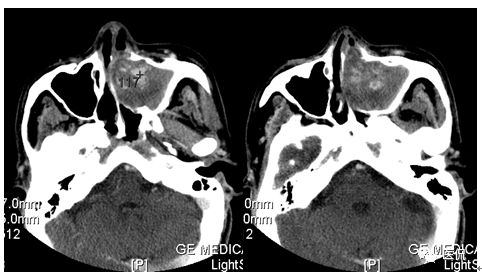

增强静脉期

CT平扫及增强示:左侧上颌窦及鼻腔可见软组织密度影,呈膨胀性生长,周围骨质压迫性吸收破坏,累及左眶,病灶密度不均匀,周边区可见点状钙化,增动脉期轻度强化,局部见小灶性稍高密度区,静脉期病灶内见不均匀明显强化,CT值最高达117HU,延迟期强化范围有所增大。

影像学表现呈软组织密度,多不均匀,表现为高低混杂密度,病变窦腔内息肉、血肿、坏死、感染共存,是病灶密度不均匀的主要原因,息肉反复出血、血管机化亦为其成因之一。病灶内钙化,可为团块状或小片状,可能为病变组织坏死后钙质沉着所致。由于病变组织内有大量炎性细胞浸润和丰富的毛细血管,增强后常有强化。有文献报道病灶增强中心区强化不明显,外周呈轻度强化,推测病灶内虽然血管丰富,但中心区容易出现血流动力学障碍,血管内常有血栓形成,中心区易发生出血坏死,另外,可能与增强扫描延迟时间选择不当有关。

本例病灶较大,周围骨质可见吸收破坏,并累及眼眶,病灶内少量钙化,增强扫描具有一定特征性,表现为动脉期轻度强化,局部见小灶性稍高密度区,静脉期病灶局部呈明显强化,CT值最高达117HU,延迟期强化范围有所增大,呈延迟渐进性强化的特点,推测为病灶内出血所致。